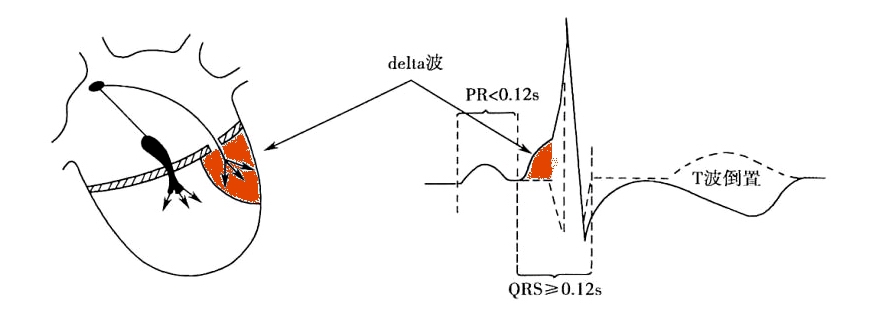

3、Δ波

Δ波又叫预激波,关键在“预”字上,如下图所示,有一个预先的电冲动传导给心室,激动部分心室(下图中左侧橙色表示的部分心肌),但心室还没有完全激动起来,如果激动起来就成了早搏了,没有完全激动的心室在心电图上的表现就是在QRS波群前面出现了一个小斜坡(下图右侧橙色小三角上的斜坡)。

如果delta波与R波都是向上的,表示预先的电冲动来自左侧旁路,也就是A型预激波,反之则为右侧旁路,即B型预激波。这点判断主要是看V1导联,当然要结合其他导联。

图9